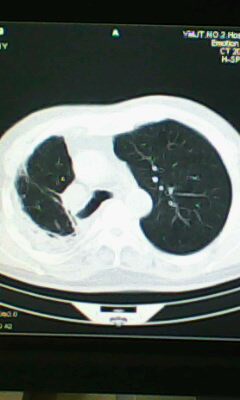

标题: CT25675:男 71 肺癌部分切除术后 3年 [打印本页]

标题: CT25675:男 71 肺癌部分切除术后 3年

两肺感染性病变,右侧肺膨胀不全,左侧上叶结节影及左侧颈部淋巴结肿大建议复查。

1)两肺感染性病变。2)右侧胸膜增厚。3)冠状动脉及主动脉钙化。

右肺炎症,左肺炎症。

右侧胸膜肥厚。

2.左肺炎症。

术后改变,双肺内纤维索条影考虑与放疗有关。